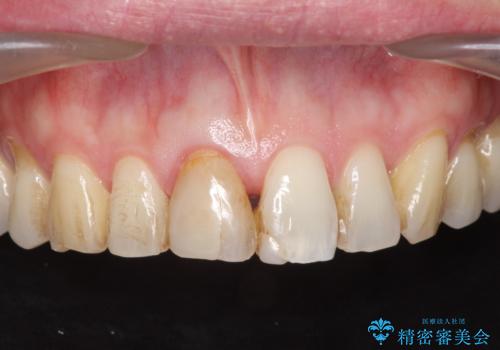

- 前歯の変色が気になり審美障害の改善を求めて来院されました。

根管治療に伴う歯の色調変化はよく見られる所見です。

セラミッククラウン製作を行い審美性の改善を計画します。